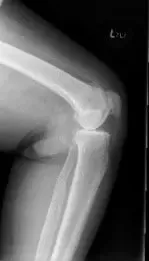

Su examen físico reveló sensibilidad articular con crepitación. Había sensibilidad en la línea articular medial y en la faceta de la rótula medial. Los estudios de imagen revelaron osteoartritis bicompartmental de la rodilla con obliteración del espacio articular del compartimento medial y del compartimento patelofemoral.

Radiografía preoperatoria de la rodilla izquierda que muestra la visión AP y lateral